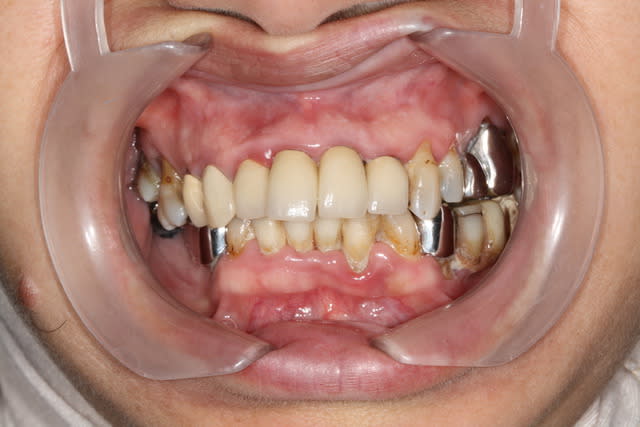

Je vous présente un cas que je viens de finir , il n'était prêt pour l'ADF . C'est un cas complet où j'ai pu exprimer mon art dans tous les domaines , endo , paro , ortho , prothèse .

J'avoue être pleinement satisfait mais j'accepte par avance et sans limitation vos remarques car le but d'un forum est de partager , voire de progresser .

Merci à tous pour vos encouragements tout d'abord . C'est très agréable de récolter des lauriers après des années d'efforts opiniâtres , ça donne un sens à notre passion .

Je me propose de commenter avec vous le traitement complet et point par point , ce débat doit rester ouvert et si Pharma75 veut intervenir c'est avec plaisir .